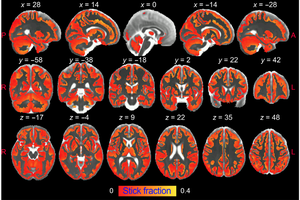

Research of the laboratories led by Dr. Silvia de Santis and Dr. Santiago Canals, both from the Institute of Neurosciences UMH-CSIC (Alicante, Spain), has made it possible to visualize for the first time and in great detail brain inflammation using diffusion-…

image: researchers from the UMH-CSIC Neurosciences Institute have developed an innovative strategy that allows imaging of microglial and astrocyte activation in the gray matter of the brain using dif… [+5951 chars]